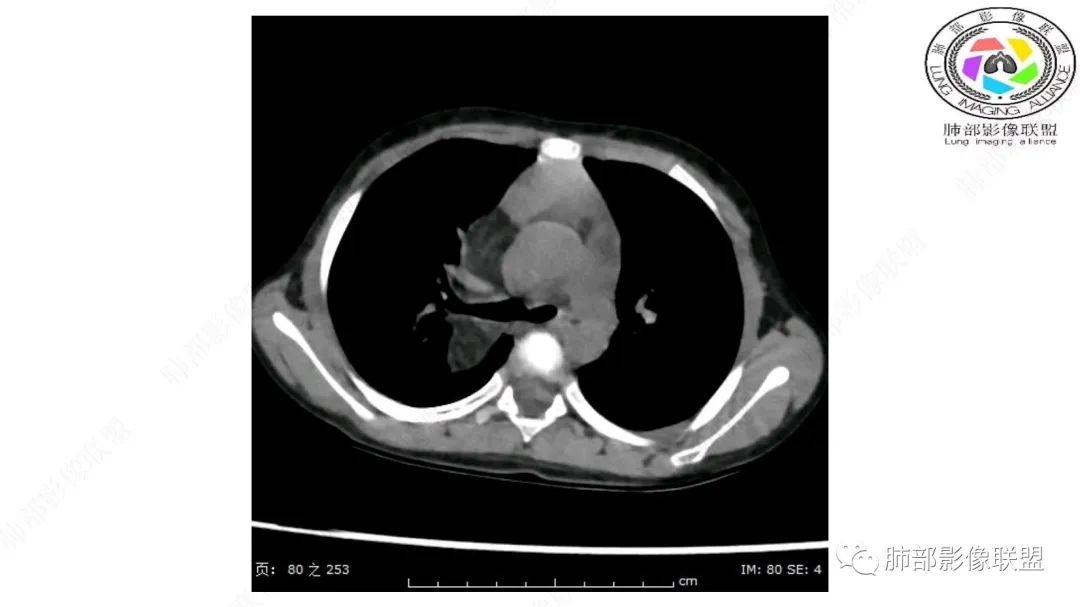

患儿3岁 咳嗽检查发现纵隔占位。右肺上叶受压表现,占位以脂肪组织密度为主,似见分隔,首先考虑为脂肪母细胞瘤,鉴别脂肪瘤,畸胎瘤。

跨肺门,包绕肺血管分支,邻近肺组织受压肺不张。

病灶属于交界区,主体位于肺内,占位效应明显,前方突入胸壁,胸腺受压变形,胸膜显示欠清楚;病灶包绕上叶肺动脉;似乎有体动脉供血。符合肺内的点:包绕上叶肺动脉分支;符合纵隔的点:前方似乎突入胸壁,与胸腺关系比较密切,但是与上腔静脉的关系提示病灶不支持纵隔来源,前纵隔的常规会将上腔静脉受压后移、外移,这是不符合的。

手术记录:见右肺上叶肿物,肿物与右肺上叶关系密切。与纵隔无粘连,逐步分离肿物,见肿物大小约6cm*5cm,边界清楚,于右肺上叶粘连,边界清楚,肿物包绕右肺上叶血管及支气管。超声刀逐步游离肿物,完整切除肿物,右肺上叶肺组织无破溃,表面无出血。

1.右上肺-纵隔交界区巨块影,主体位于右肺一侧,紧贴胸腺、头臂干、右锁骨下动脉、上腔静脉、奇静脉等,不能分离,但病灶整体边界清楚。注意上述相邻腔静脉等结构未见受压变形,纵隔亦未见明显向左推移,至少提示两点:

1)病灶相当柔软。

2)位于纵隔内或纵隔胸膜的可能性较小,因为受纵隔胸膜反作用力影响不明显。

2.肺动脉穿行也许是肺内来源最重要支持点!

CT扫描对脂肪类肿瘤常有独到价值。肿块孤立、边界清楚,未见周围浸润,较均匀脂肪样低密度,高度提示为良性!

发生于成人为脂肪瘤表现,婴幼儿自然会想到脂肪母细胞瘤。两者生物学行为并无本质区别。